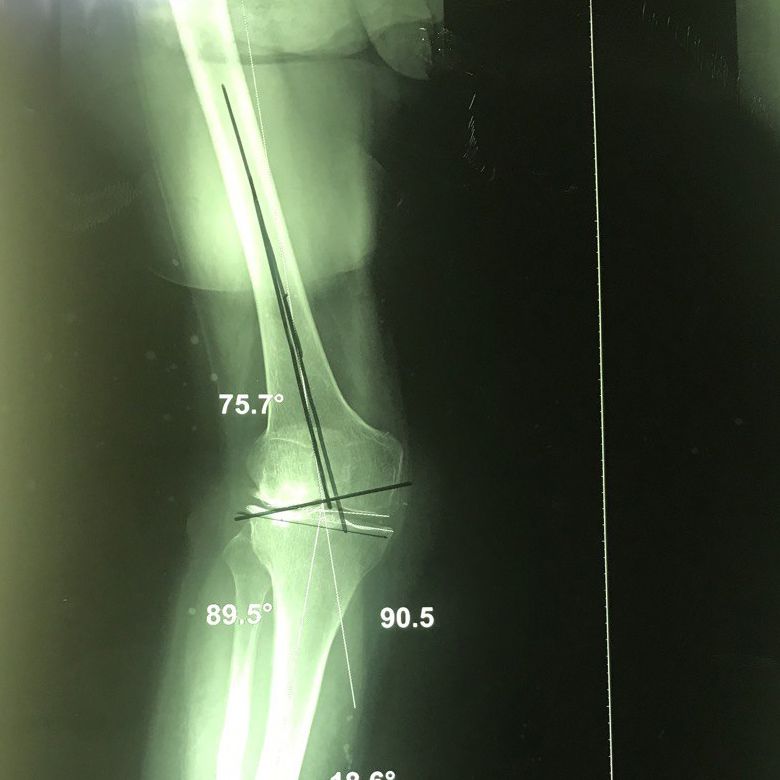

Axial deviation of the knee

Axial deviation of the knee is one of the structural disorders of the knee and can be seen in the form of a bracketed or crossed knee.